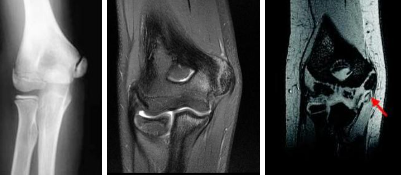

Figure 1 shows a coronal T2-weighted MRI scan. What is the name of the labeled torn structure?

LCL, and it is avulsed from the lateral humeral epicondyle. This is the most common site of injury for the LCL. The biceps and brachialis tendon insertions are not well visualized in this section. The MCL and flexor/pronator origin are intact.